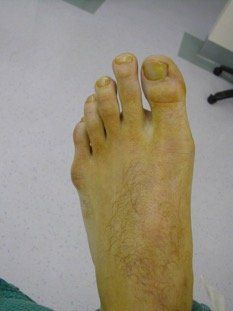

A Tailor’s bunion refers to hypertrophy (prominence) of the fifth metatarsal head. Often the prominence is symptomatic and irritation can be due to osseous (bony) or soft tissue thickening, and pressure from footwear. There may also be an associated deformity of the fifth toe.

Surgical correction of your Tailor’s bunion head may be required when it is painful such that it X-ray photo of left foot Tailor’s bunion showing sharp interferes with normal daily activity, or there bony prominence are footwear fitting difficulties.